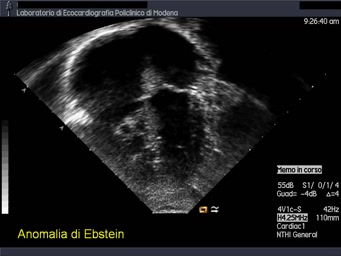

Titolo:

Ebstein

Autore:

Andrea Barbieri